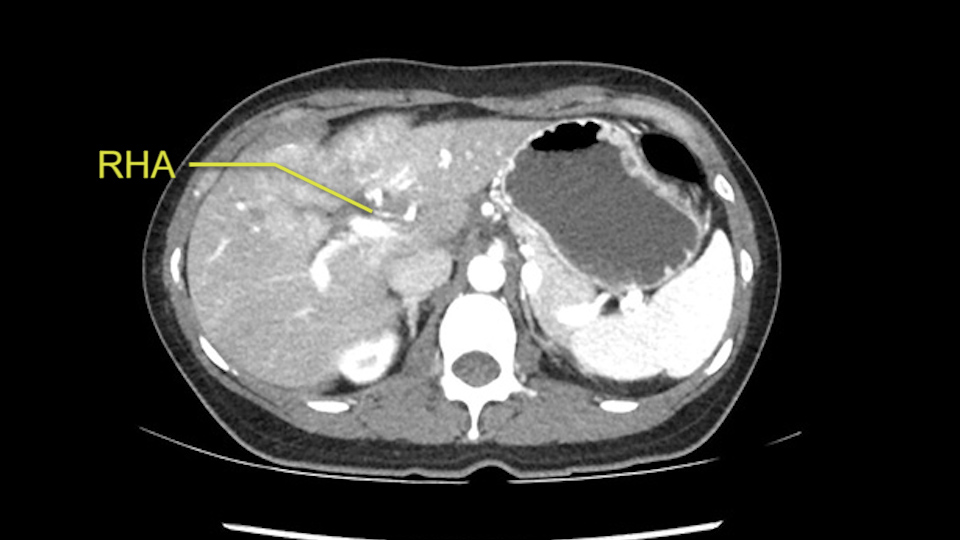

The second is the left hepatic artery. The tumor is displacing the arterial system. So one of the important points which we need to see intraoperatively is to identify and preserve the right artery very carefully and identify the left hepatic artery for ligation.

RHA, Sg4 artery not involved in tumor

So in planning for this operation, as I look at the scans, I first visualize the arterial phase and I can see that there’s are a lot of big feeding arteries to this large tumor. Likely all the right side vessels feeding the right side of the liver: right hepatic artery and likely the Segment 4 artery are spared from the tumor. It’s likely the left hepatic artery is ramificating and giving feeding arteries to this tumor. It certainly looks like a large mass that its compressing other structures like the cava, the pancreas, the stomach; but I think there’s a plane and we can see that better in the venous phase. There’s a plane of separation between the gallbladder, the pancreas, the cava, that this tumor is abrupting but likely not invading. Usually, these masses actually don’t invade at that level and basically are pushing the tissues and once you open, you’re able to separate the tumor. Sometimes there’s some adhesions but you can actually separate and there’s usually no invasion.

Muchas ramas de la arteria hepática izquierda al tumor

Estructuras vasculares derechas estan libres de tumor